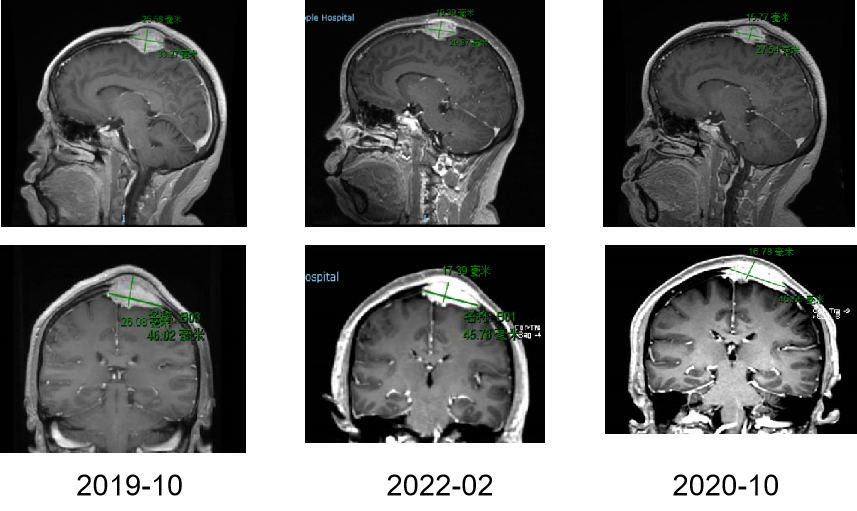

图4